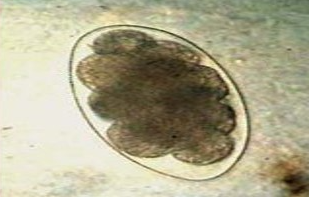

This was found in a stool sample of a young scouring pig. What is it?

Ascaris suum - large roundworms of pigs (egg)